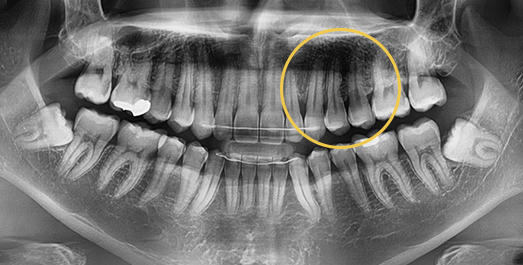

매복치 Solution

매복치는 잇몸 속에서 인접 치아에 손상을 줄 수 있어

치아 견인을 통해 제자리를 찾아주어야

정상적으로 치아가 자리잡을 수 있습니다.

-

BEFORE: 2011.08.12

AFTER: 2013.07.08